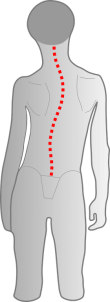

Die Verformung des Schädels schließt auch die Schädelbasis mit ein und da auch die Halswirbel noch verformbar sind, können sich diese nun ebenfalls asymmetrisch zueinander verschieben. Hierbei kommt es nun zu einer reduzierten Kopf- und Wirbelsäulenmobilität. Das Ganze kann durch eine Vorzugshaltung hin zu einer Lieblingsseite des Säuglings nochmals verstärkt werden. Wenn sich die Kinder dann zum Sitzen und Stehen aufrichten, wird häufig der Kopf schief gehalten – was zu einer skoliotischen Fehlhaltung führen kann. Die Muskeln werden einseitig stärker beansprucht und verspannen deutlicher, was sich in Schulter-, Nacken- und Kopfschmerzen ausdrückt. Inwiefern das auf die Nervenbahnen drückt und Auswirkungen auf die Verdauung hat, kann nicht abschließend beantwortet werden. Wird dies jedoch nicht behandelt, kann die gesamte Körperwahrnehmung gestört werden, was sogar noch bei Erwachsenen ausgeprägt ist. Langfristig kann das ebenfalls zu weiteren Rumpfasymmetrien führen.